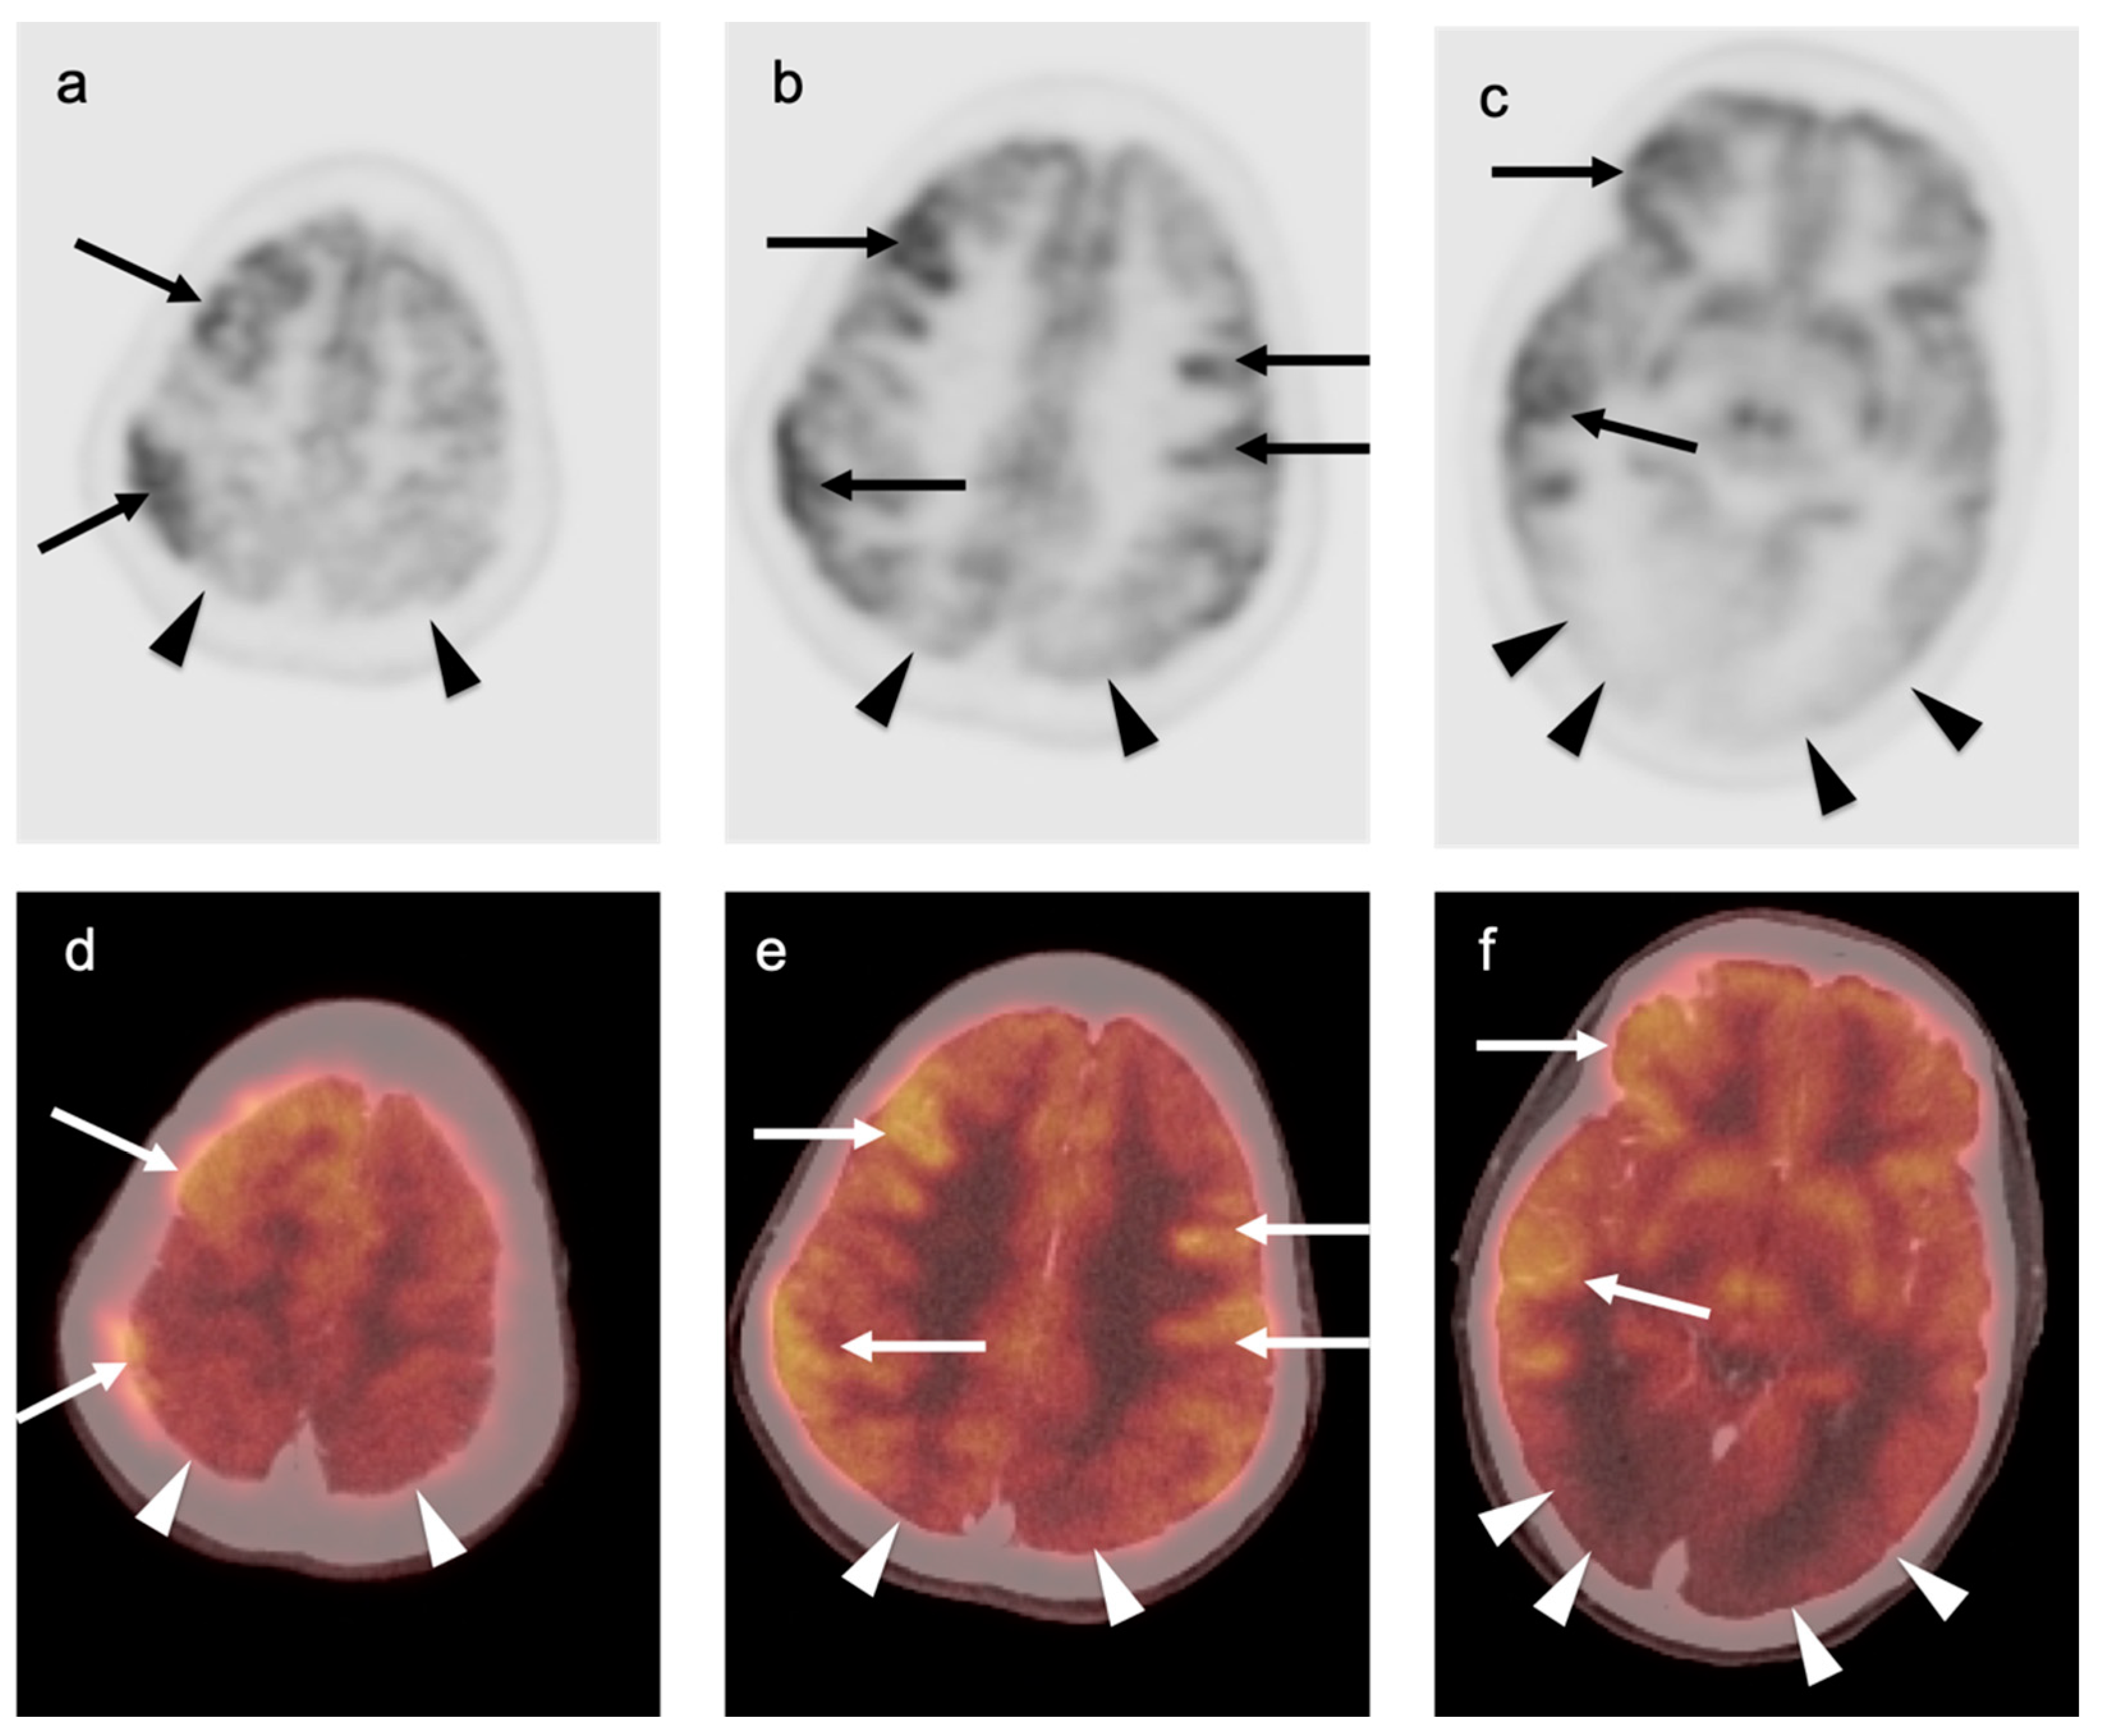

3.4. CNS Lymphoma

3.5. Brain Metastases